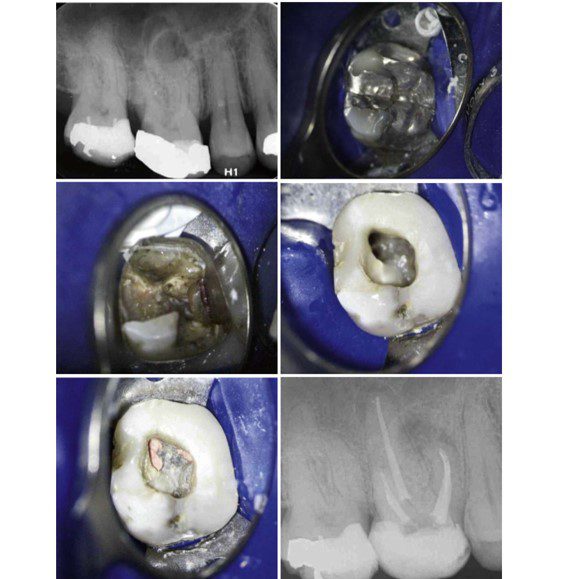

Trường hợp mất mô răng quá nhiều thì nên tái tạo lại thân răng để dễ dàng đặt cách ly, có thể sử dụng GIC hoặc composite (H7.8).